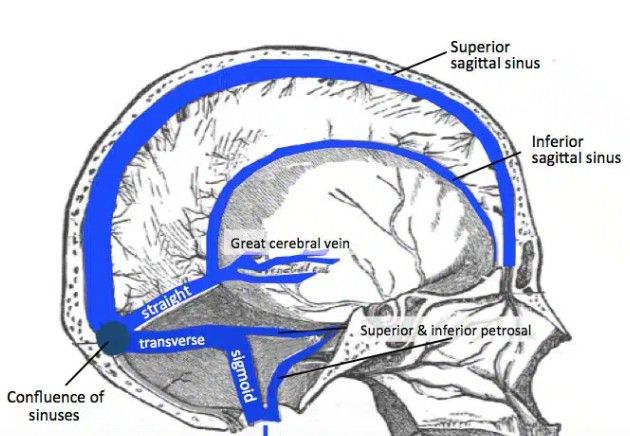

Superior sagittal sinus

Inferior sagittal sinus

Straight sinus

Transverse sinuses

Sigmoid sinuses

Superior sagittal sinus: runs in falx cerebri → drains to confluence of sinuses (1)

Inferior sagittal sinus: joins great cerebral vein → forms straight sinus (1)

Straight sinus: drains to confluence (1)

Transverse sinuses: from confluence → become sigmoid sinuses (1)

Sigmoid sinuses: drain into internal jugular vein (1)

Cavernous sinus: drains via superior & inferior petrosal sinuses (1)- Cavernous Sinus Detail (3 marks)

Confluence of sinuses = meeting point (superior sagittal, straight, occipital)

Internal jugular vein is final drainage pathway